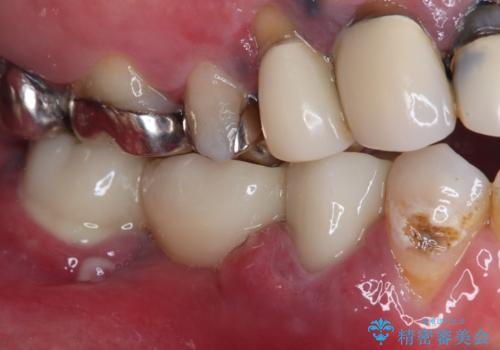

- ブリッジが装着されている奥歯がぐらぐらするとのことで来院された患者様です。

診察を行ったところ、手前の歯は歯根が破折しており、抜歯が必要な状態でした。

左右ともに臼歯部しか咬んでおらず、ブリッジの手前側の歯が破折したことで大きく揺さぶられてしまい、奥側の歯も周辺の歯が著しく吸収し、抜歯が必要な状態でした。

ブリッジの支台歯2本を抜歯し、反対側の咬合負担を軽減するために、通常よりも短い待機時間で2本のインプラントを埋入することとしました。